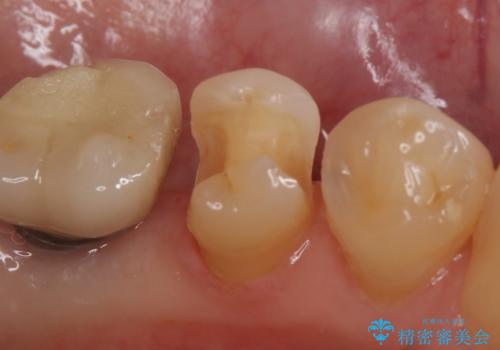

- 左下5番目の銀歯が気になるのでセラミックにしたいといらっしゃった方の症例です。

銀歯及び虫歯を除去後、セラミックインレーによる修復を行いました。

当院のセラミックインレーはemaxという強度と審美性に優れた材料を使用しています。

またプレス方式でインレーを製作しているため、削り出しで製作するCADCAMより優れた適合性も持ち合わせており、虫歯が再発しにくい修復物です。